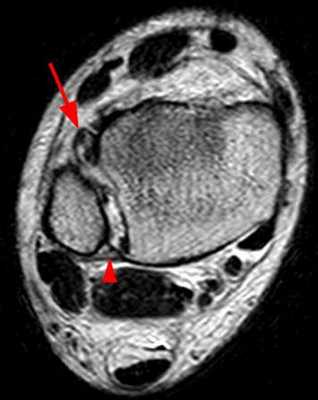

При подозрительной на разрыв межберцового синдесмоза клинической картине и отрицательных результатах рентгенографии рекомендуется выполнение КТ или МРТ. Они позволяют выявить частичные повреждения. Также их роль неоценима в оценке качества устранения межберцового диастаза после операции.

В диагностике важную роль играет сонография и МРТ, часто при обследовании выявляются такие аномалии как 4-я малоберцовая мышца, низко-расположенное брюшко короткой малоберцовой мышцы.